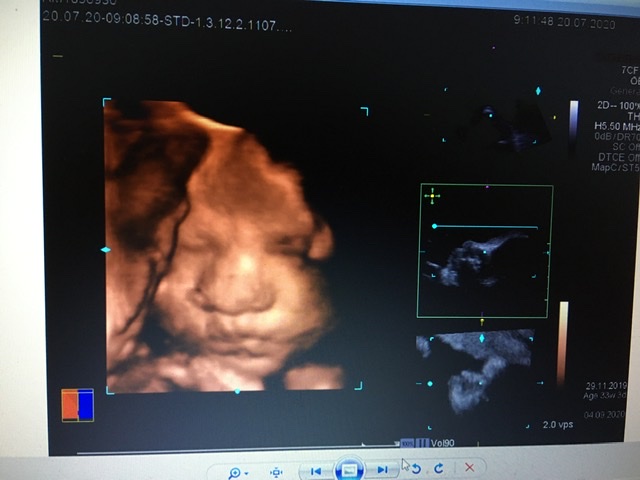

Все будет видно) но мне узист советовал в 28) там уже прям человек))мы почти в 27 делали если считать по 1 скринингу. Очень долго пытались выловить лицо,сынуля каждое узи показывает писюн)))личико прячет. Мы не пожалели,что сходили 😍нам понравилось. Он там зевал,показывал язык )))ну и складывал на лицо все,что можно..ручки,ножки,пуповину)))

вот в 34 ещё делали)) Обычно все детки поджимают нижнюю губу,наш наоборот,выпячивает 😀ой,я так рада была,когда увидела его губы))) у мужа пухлые,красивые,как раз хотела,чтобы как у мужа были))